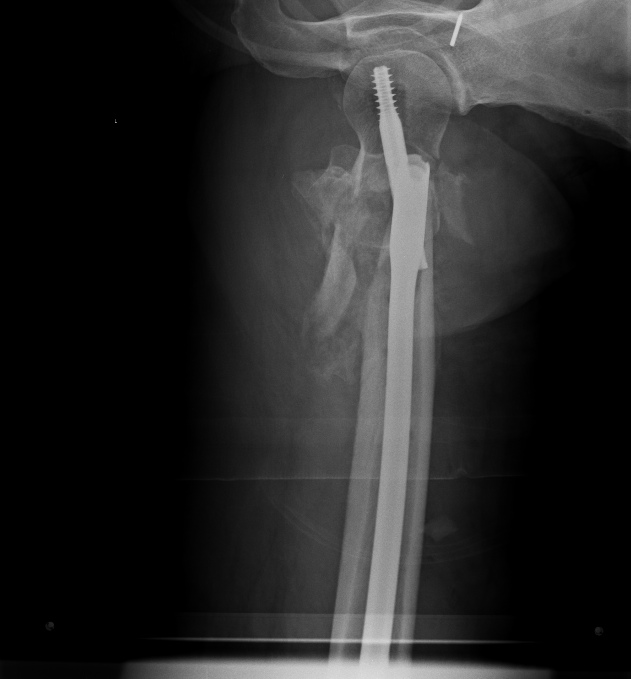

Круто, на самом деле. И отломок проксимальный из флексии убрали и в

вальгус перевели и шеечный винт как-то умудрились зацепить в головке.

>  асибо за интересное обсуждение. Действительно, головка сохраняет

> сферичность, кровоснабжение ее должно быть сохранено, так что есть смысл

> сделать реконструкцию.

> Удалили  DHS, пришлось вытащить единым блоком, винт прокручивался. .

> Опознавательных знаков на имплантате не обнаружили. Дополнительный винт был

> введен во фрагмент, который оказался не связан ни с чем, так что удалили и

> его После удаления была хорошая подвижность. Сделали остеосинтез вот так.

> Комментарии и критика приветствуются.